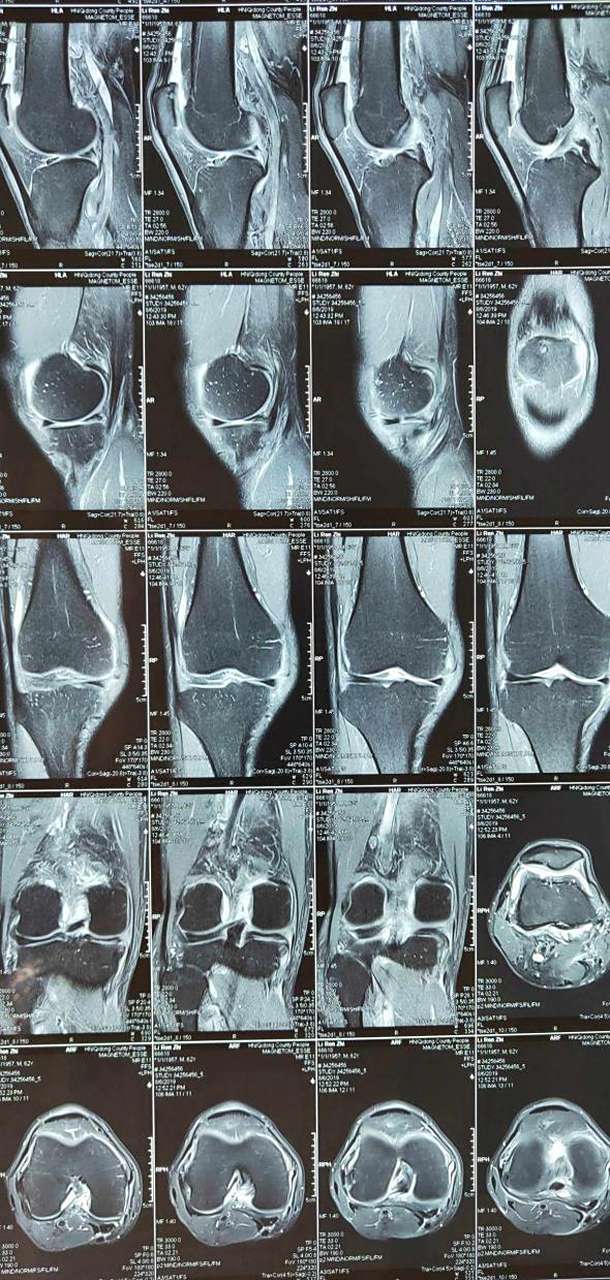

是什么意思内外侧半月板后角损伤半月板撕裂内侧膝盖半月板撕裂磁共振

图片尺寸900x1200